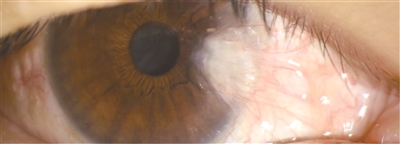

通过专业的裂隙灯显微镜观察小伙子的右眼:右眼球表面(结膜)上,长出了一片异常增生组织,形状有点像“昆虫翅膀”,向中央的“黑眼球”(角膜)延伸……

医学上,我们将小伙子眼内的异常增生组织称之为翼状胬(nǔ)肉。翼状胬肉也称为角膜上皮翼状胬肉,主要发生在眼角膜表面的角膜上皮组织中。它通常表现为一块略微隆起、有时带有血丝的、呈翼状或菜花状的物质,因形状似昆虫的翅膀而得名。